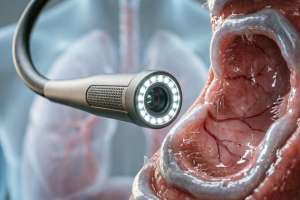

ما هو تنظير القصبات؟

فيما يلي محتوى موسوعة منظمة حول تنظير القصبات، اتبع متطلباتك بدقة:الفقرة 1: نظرة عامةمنظار القصبات هو جهاز طبي يستخدم لمراقبة البنية الداخلية للقصبة الهوائية والشعب